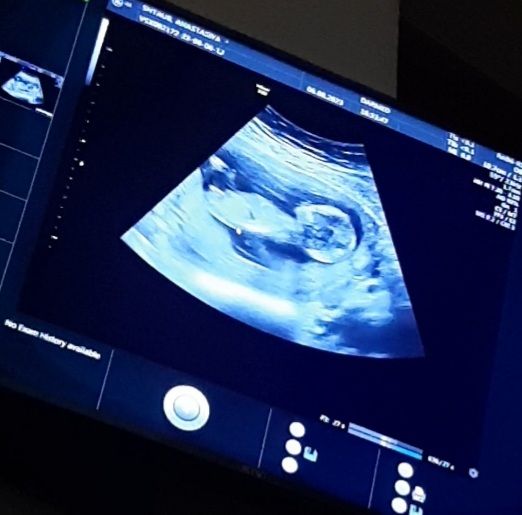

Результаты скрининга на 12-13 неделе: 80% вероятность девочки. Нужна помощь в сравнении снимков!

Изображение А вот в 17+3 дня